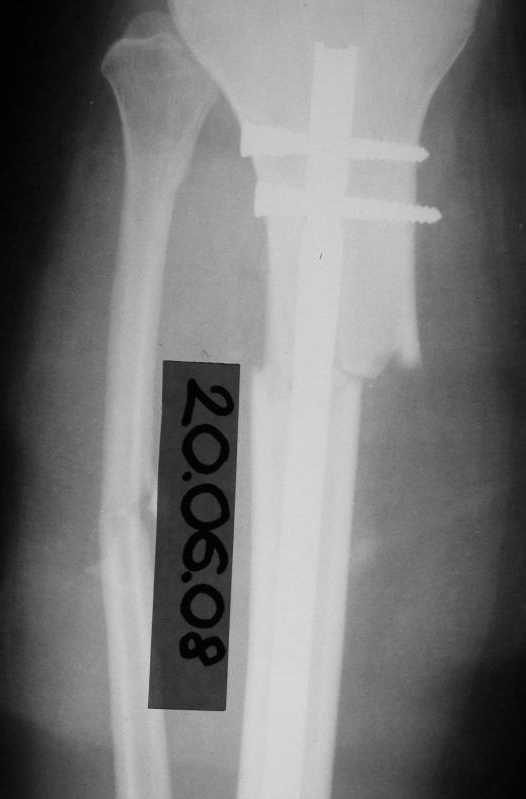

История следующая: женщина (медработник)сбита машиной 7.06.08 - о.перелом обоих костей голени в/3 со смещением. В ПДО ПХО раны,вытяжение за пяточную кость. После заживления раны 20.06.08 выполнен остеосинтез блокирующем стержнем. в течение первого месяца после травмы сохранялась субфебрильная температура на фоне приема антибиотиков. Затем температура стабилизировалась.Б-ая как положено ходила в гипсе на костылях. На контрольных рентгенограммах консолидация не достигалась, иммобилизация продлевалась. Пациентка на себе опробовала все препараты костной регенерации. В марте удален один из фиксирующих винтов. На сегодняшний день идет 11 мес. после травмы. Решается вопрос о инвалидности. Буду благодарен за предложения по дальнейшему ведению больной. Операция?

А разве полежено после остеосинтеза блокировиным стержнем применять гипс:???????????? Через 8 месяцев делать динамизацию не позно ли? При этом, я думаю, нужно было бы сделать остеотомию малоберцовой кости, которая срослась и мешает отломкам двигатся при нагрузке.Я думаю можно сначала сделать остеотомию малоберцовой кости и удалить и верхний винт и дать нагрузку.

Сегодня мы имеем консолидированный перелом малоберцовой кости, являющийся распоркой и отстутствие консолидации большеберцовой кости, и ваша динамизация гвоздя, выполненная с опозданием не ришила проблем.

Судя по изменению положения гвоздя в послеоперационном периоде (хотя и в благоприятную сторону) нестабильность была очевидна. И не стоило

пытаться решить проблему гипсом, надо было сразу делать ревизионный остеосинтез. В итоге пациент бы не потерял год на лечение.

Судя по разнице послеоперационных и последующих снимков, с самого начала уже была задана "гипердинамизация", раз положение отломков изменялось буквально на сантиметры.